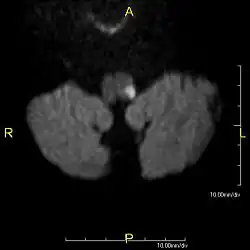

La lésion sera le mieux vue sur une IRM cérébrale.